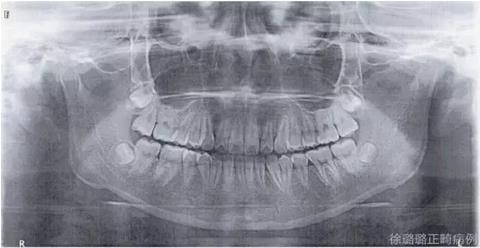

影像學(xué)檢查

X 線檢查:替牙列,上頜雙側(cè)尖牙埋伏阻生(含牙囊腫),四顆第三恒磨牙牙胚存在。

前牙 CT 檢查:上頜雙側(cè)尖牙埋伏阻生——雙側(cè)尖牙的牙冠均在側(cè)切牙根方的唇向位。

CT 片結(jié)果顯示,上頜雙側(cè)側(cè)切牙與尖牙位置較近,因此早期沒有粘結(jié)雙側(cè)側(cè)切牙托槽,以防止正畸加力對牙齒造成根尖吸收。